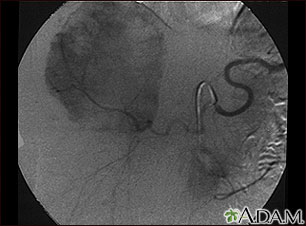

- Hepatic angiogram